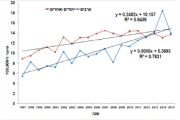

| 17:38, 16 בספטמבר 2023 | מלנומה יהודים1.png (קובץ) |  |

31 קילו־בייטים | Motyk | 1 | |

| 17:06, 16 בספטמבר 2023 | מלנומה יהודים.png (קובץ) |  |

64 קילו־בייטים | Motyk | 1 | |

| 16:07, 16 בספטמבר 2023 | מלנומה לפי גיל.png (קובץ) |  |

36 קילו־בייטים | Motyk | 1 | |